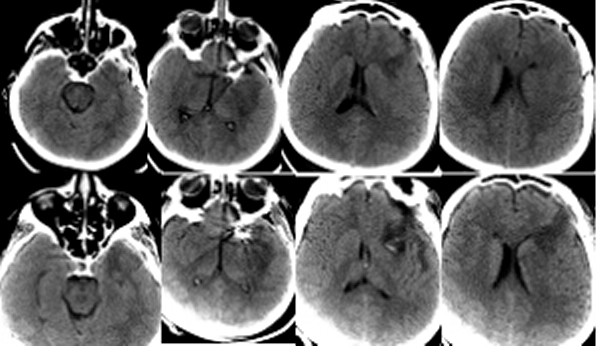

Пациентка Ч, 41 года, поступила в Институт с диагнозом: множественные аневризмы сосудов головного мозга – гигантская эксцентричная фузиформная аневризма области бифуркации левой ВСА с распространением на М1 сегмент левой СМА и аневризма небольших размеров развилки правой ВСА, рецидивирующие субарахноидальные кровоизлияния (САК), подострая внутримозговая гематома области Сильвиевой щели слева. Пациентка дважды переносила САК из аневризмы левой ВСА: за 1,5 месяца и 7 суток до госпитализации в Институт. При поступлении больная предъявляла жалобы на умеренную головную боль, очаговой неврологической симптоматики не выявлялось, по шкале Ханта-Хесса тяжесть состояния оценивалась в 1 балл. Ввиду гигантского размера и фузиформного характера аневризмы операция была технически сложной: проводилось многократное временное клипирование (по 5-7 мин) задней соединительной артерии, левой передней мозговой артерии, общей и наружной сонной артерии на шее, многократное репозиционирование клипсов на шейке аневризмы, внутрисосудистая аспирация крови из левой внутренней сонной артерии. По данным допплерографии наблюдалось преходящее снижение кровотока в дистальных отделах М1 сегмента левой СМА, что потребовало дополнительного пережатия общей и наружной сонной артерии на шее в течение 9 мин. Была также удалена гематома левой височной доли. Через 1,5 часа после завершения операции на фоне пробуждения из наркозного сна и появления реакции на интубационную трубку выявлялся правосторонний гемипарез, инструкций пациентка не выполняла. В контексте особенностей проведенной операции состояние было расценено как формирующееся ишемическое повреждение мозга, и было принято решение о незамедлительном начале ИГ для защиты головного мозга. ИГ проводилась в соответствии с описанным выше протоколом. КТ головного мозга выявило послеоперационные изменения (Рисунок 1).

Через 1,5 часа после завершения операции на фоне пробуждения из наркозного сна и появления реакции на интубационную трубку выявлялся правосторонний гемипарез, инструкций пациентка не выполняла. Состояние было расценено, как формирующееся ишемическое повреждение мозга, и было принято решение о незамедлительном начале ИГ для защиты головного мозга. ИГ проводилась в соответствии с описанным выше протоколом. Гипотермия была достигнута в течение 3,5 часов. Гемодинамика была стабильной. Проводилось энтеральное питание. Лабораторные показатели были в пределах нормы. Гипотермия продолжалась в течение 2 суток, после чего было начато согревание. Седация была прекращена при достижении нормотермии. Неврологический дефицит отчетливо регрессировал: восстановились сознание и движения в правых конечностях. При контрольном КТ-исследовании головного мозга очагов ишемии не выявлялось (Рисунок 1). Температура оставалась в пределах нормы, поэтому охлаждающий катетер был удален на следующий день. Осложнений ИГ не было. ИВЛ продолжалась еще в течение 4 суток. После экстубации пациентка наблюдалась в отделении реанимации еще 2 суток. Из Института больная выписана на 23 сутки после операции в удовлетворительном состоянии без очагового неврологического дефицита.